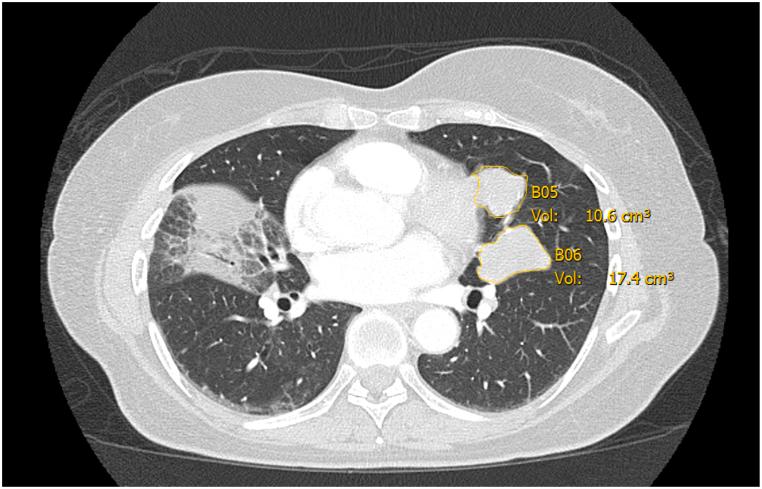

Adenoid cystic carcinoma (ACC) is a rare salivary gland cancer. The vast majority of clinical trials evaluating systemic therapy efficacy in solid tumors use the Response Evaluation Criteria in Solid Tumors (RECIST) to measure response that is limited to 2 dimensional only evaluations, not taking volume or density into account. The indolent behavior ACC represents a challenge toward an appropriate evaluation of therapy response. Objectives: 1) To describe and contrast volumetric and density changes at each time-point, including changes noted from baseline to best response, to currently used 2 dimensional-only criteria (RECIST) and 2) To report the coefficient of variation in volume measurement among three reviewers on a subset of ACC patients.

We retrospectively assessed a cohort of 18 prospectively treated patients with ACC in a phase 2 trial with vorinostat using a volumetric (viable tumor volume, VTV) and density criteria. Three independent and blinded observers segmented target lesions across a sample of randomly selected computed tomography (CT) exams to examine inter-observer variation.

We found that the average coefficient of variation among observers for all target lesions was 16.1%, with lung lesions displaying a smaller variation at 14.0% (p-value >0.17). We describe examples of decrease in volume and density in several lesions despite stable disease by RECIST.

腺样囊性癌(ACC)是一种罕见的唾液腺癌。绝大多数评估实体瘤全身治疗疗效的临床试验使用实体瘤疗效评价标准(RECIST)来衡量反应,该标准仅限于二维评估,未考虑体积或密度。ACC的惰性行为对治疗反应的恰当评估构成挑战。目的:1)描述并对比每个时间点的体积和密度变化,包括从基线到最佳反应的变化,与目前仅使用的二维标准(RECIST)进行对比;2)报告在一部分ACC患者中,三位评估者对体积测量的变异系数。

我们回顾性评估了一项在2期试验中使用伏立诺他对18例前瞻性治疗的ACC患者的队列,采用体积(存活肿瘤体积,VTV)和密度标准。三位独立且不知情的观察者在随机选择的计算机断层扫描(CT)检查样本中对靶病变进行分割,以检查观察者间的差异。

我们发现,所有靶病变观察者间的平均变异系数为16.1%,肺部病变的变异较小,为14.0%(p值>0.17)。我们描述了几个病变尽管按RECIST标准疾病稳定,但体积和密度却减小的例子。